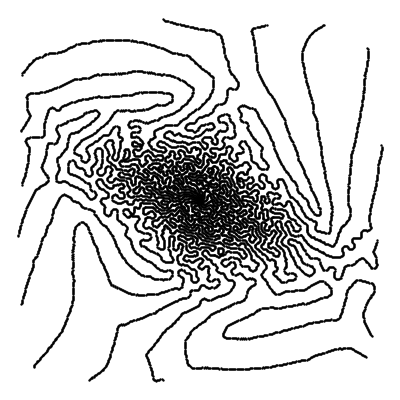

Trajectories in k-space

|

Angles of the shots

Kernel blurs

In our experiments, we consider a subsampling ratio of and , meaning that or respectively. The parameter encodes all the parameters above. The sensitivity maps and the trajectory perturbations are usually unknown, making MRI reconstruction a blind inverse problem. Examples of realistic sampling trajectories used in this work are displayed in Fig. 2, bottom.

The most common way to parametrize the Point Spread Function (PSF) of an optical system in optics is by using Fresnel diffraction theory [13]. In this theory, the PSF is entirely determined by the pupil function, which is a complex function defined over the objective aperture. For a circular aperture, the pupil function can be expanded with Zernike polynomials, which are orthogonal polynomials over the disk [68, 53]. The parameter coincides with the coefficients of this linear decomposition. The problem is blind whenever the PSF is unknown. In our experiments, we consider a linear combination of Zernike polynomials. Examples of random PSFs generated through this model are displayed in Fig. 2, top.

Following [36], we generate random target densities as anisotropic power decaying distributions. They are parameterized by a random vector that encodes the density at origin, the anisotropy and the power decay law. To avoid solving (13) at training time, we have pre-computed sampling patterns. The corresponding vectors have been generated by using a max-min sampling (see [72, 25]) of a set of an admissible set of parameters . We refer to [36] for more details. Examples of densities and sampling patterns without constraints are displayed in Fig. 2(a)-2(e). Notice that we did not include trajectory constraints for generating this figure. They are taken into account for the blind inverse problem part.